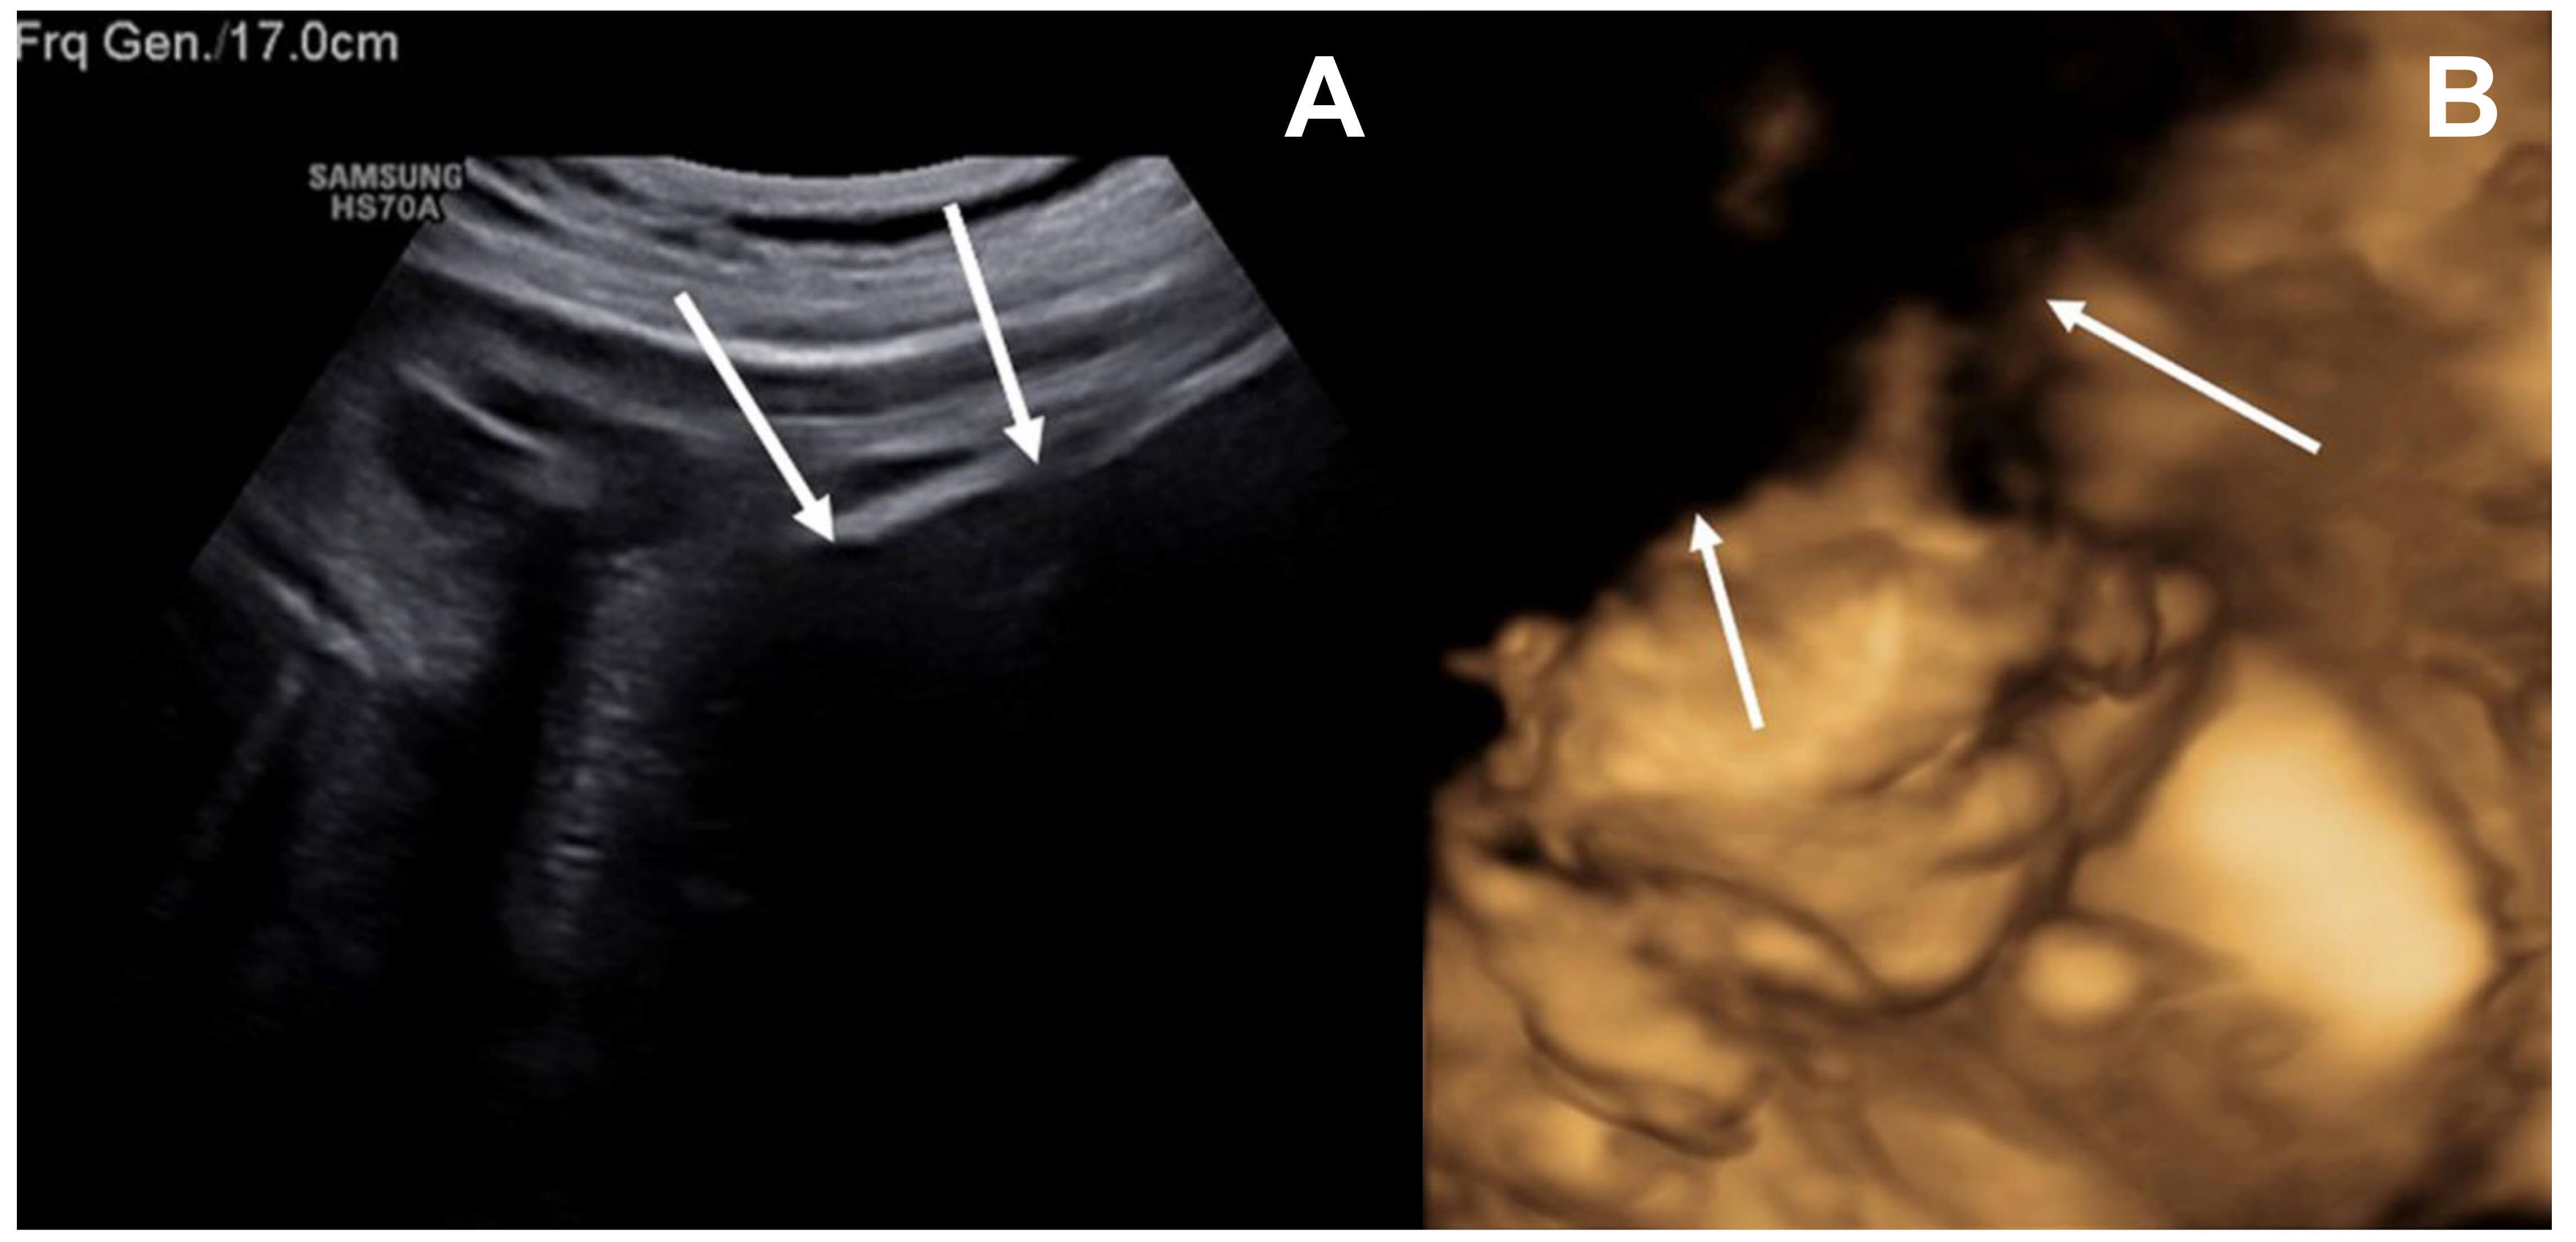

At our institution, repeat ultrasound failed to clearly visualize the fetus, as the maternal lower abdomen was obscured by a large, ill-defined hypoechoic, mass-like area, suggestive of a non-native soft tissue component interfering with acoustic penetration. The mass appeared to occupy the subcutaneous and potentially deeper fascial planes, although precise delineation was limited by the imaging modality (Fig. 1A,B). After conducting fetal ultrasound examinations over an extended period and from multiple angles, no structural abnormalities were detected in the fetus, and no abnormal findings were observed in the amniotic fluid, although placenta previa was noted.

Fig. 1.

Maternal lower abdominal hypoechoic mass limiting acoustic penetration on fetal ultrasonography. (A) Ultrasound imaging was limited by a large hypoechoic mass-like lesion in the maternal lower abdomen, which impeded adequate acoustic penetration. (B) A portion of the fetal face was not visualized on the three-dimensional ultrasound due to the presence of a maternal lower abdominal hypoechoic mass-like opacity. White arrows highlight the hypoechoic mass-like region interfering with acoustic penetration.